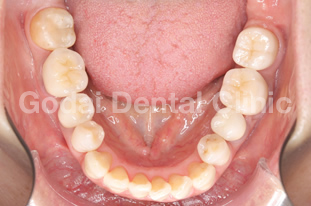

患者様は20代男性、虫歯の治療をしたいことと、歯並びを改善したいという主訴で来院されました。歯医者は10年以上ぶりですが、虫歯も歯並びもしっかり治したいという希望を持っていました。久しぶりの歯医者ということもあり、まずは歯磨きの仕方から改善していきました。歯垢をブラッシングで除去できるようになったところで、虫歯の治療を開始しました。歯並びが悪いこともあり、多くの歯に虫歯が見つかりました。患者様の年齢と歯質の保存を優先し虫歯の治療はコンポジットレジン修復を行いました。また下の親知らずが横向きに生えていたため、左右の親知らずの抜歯を矯正前に行いました。

歯ブラシの改善と虫歯の治療、親知らずの抜歯が終わったところで、矯正治療へ移行しました。患者様は健康な歯を抜きたくないという希望を持っていたので非抜歯の治療計画を立てました。まずは上下顎ともに拡大装置を用い歯列の拡大を行いました。その後、アライナーを使ったインビザライン矯正治療へ移行し、歯並びの修正と咬み合せの確立を行いました。拡大装置を使っている際は、口内炎や話しずらさなどがあったそうですが、インビザライン治療に移行してからは痛みも話しずらさもなくなり快適に過ごせたそうです。もともと多くの虫歯があったため矯正中の虫歯が心配でしたが、インビザライン矯正治療を選択したことで、新しい虫歯を作らずに治療を終えることができました。

歯並びを改善したい場合でも、歯磨きの確立、虫歯の治療、親知らずの抜歯など矯正前に治療が必要な場合もあります。ただ矯正前の治療をしっかりと行うことで、矯正治療の結果がより良いものになりますし、治療もスムーズに進みます。最終的に患者様にとって最善の治療になるよう心がけて治療を行っています。口の中が心配な方は、いつでもご相談ください。

治療前1

治療後1

治療前2

治療後2

治療前3

治療後3

治療前3

治療後3

治療前3

治療後3